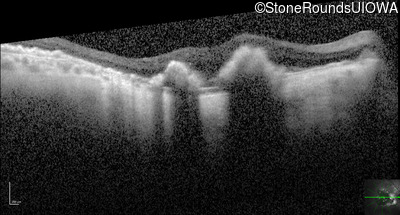

Optical Coherence Tomography - Right - Count Fingers 6'

Exemplar / OCT Stack

OCT Stack